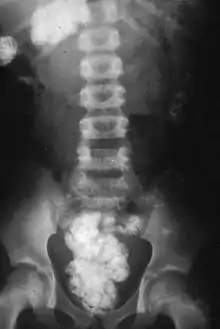

Human geophagia is a form of pica – the craving and purposive consumption of non-food items – and is classified as an eating disorder in the Diagnostic and Statistical Manual of Mental Disorders (DSM) if not socially or culturally appropriate.[6] Sometimes geophagy is a consequence of carrying a hookworm infection. Although its etiology remains unknown, geophagy has many potential adaptive health benefits as well as negative consequences.[5][7]

There are obvious health risks in the consumption of soil that is contaminated by animal or human feces; in particular, helminth eggs, such as Ascaris, which can stay viable in the soil for years, can lead to helminth infections.[43][44] Tetanus poses a further risk.[43] Lead poisoning is also associated with soil ingestion,[45] as well as health risks associated with zinc exposure can be problematic among people who eat soils on a regular basis.[32] Gestational geophagia (geophagia in pregnancy) has been associated with various homeostatic disruptions and oxidative damage in rats.[46]